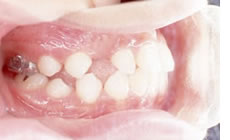

■治療中

奥歯がかなり後ろに下がり、犬歯が生えるためのスペースが確保できました。